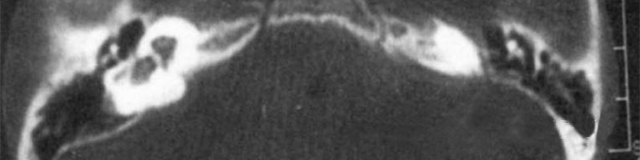

1、診斷

主要依靠顳骨高分辨CT和內(nèi)耳MRI。

雙側(cè)內(nèi)耳畸形:左側(cè)無內(nèi)耳迷路及內(nèi)耳道機(jī)構(gòu),為米歇爾畸形;右側(cè)空耳蝸及前庭擴(kuò)大,為先天性耳蝸畸形